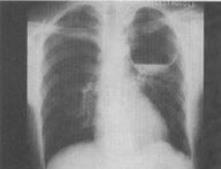

- 单项选择题 患者男,26岁,胸闷、胸痛3个月余,胸片如图,最可能的诊断为()。

A、左上肺空洞型结核

B、左上肺脓肿

C、左上肺液气囊肿

D、左上肺包虫病

E、韦格肉芽肿

- C